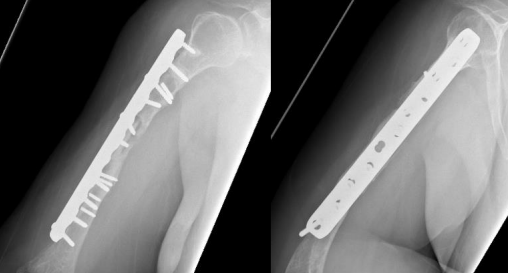

At that time, the primary surgeon decided to transfer the case to the Trauma unit, where the patient was reviewed thoroughly and all necessary investigations was made, after detailed discussion of the case and the options, we decided to go for another revision but with some tactical modifications. The patient was taken for yet another surgery, for the fifth time (fourth revision) on 30 November 2020. The same incision site was used, and the previous plate was removed and sclerotic bone debrided. An intramedullary cancellous bone graft was obtained from the patient’s left femur with the aid of a reamer-irrigator-aspirator. A titanium mesh cage was used to bridge the bone defect, and the graft from the left femur intramedullary canal was packed inside the titanium mesh cage. Primary fixation was obtained with a long proximal humerus locking plate laterally and augmented with a 3.5 cm locking compression plate anteriorly sat 90 degrees orientation.

Finally, 5.6 mL of rhBMP-2, on an absorbable collagen sponge carrier (ACS), was applied to the nonunion site. Postoperative radiographs are shown in Figure 8. Postoperatively, the patient suffered radial nerve neuropraxia, managed with splinting, and fully recovered 5 months postoperatively. Serial follow-ups for 21 months postoperatively showed complete healing clinically and radiographically, restoration of functional range of motion with the help of physiotherapy, and a painless functional limb. Radiographs are shown in Figure 9.

Figure 08

Final revision surgery was performed with an intramedullary bone graft from the patient’s left femur, together with a titanium mesh cage to bridge the bone defect. The graft from the left femur intramedullary canal was packed inside the titanium mesh cage, and primary fixation was obtained with a long proximal humerus locking plate laterally, augmented with a 3.5 cm locking compression plate anteriorly. Finally, 5.6 mL of rhBMP-2 on an ACS was applied to the nonunion site.